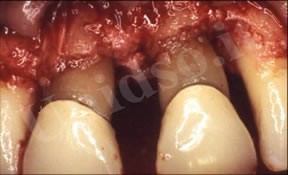

L’ Unità Operativa di Parodontologia e Igiene Orale si compone di 5 sezioni. L’attività’ clinico-assistenziale è svolta da diversi odontoiatri, supportata da igienisti dentali e assistenti alla poltrona, ed è articolata sulla base di appuntamenti programmati. Nell’Unità Operativa di Paradontologia e Igiene Orale del DSMOB si eseguono le seguenti prestazioni odontoiatriche: istruzioni d’igiene orale, ablazione tartaro, full radiografico, terapia dell’alitosi, levigatura radicolare, chirurgia parodontale riparativa, resettiva e rigenerativa e chirurgia plastica dei tessuti molli parodontali.